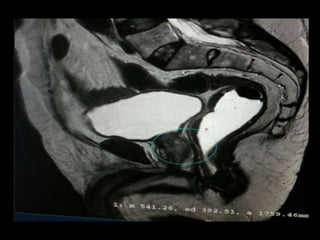

RM OBSTÉTRICA